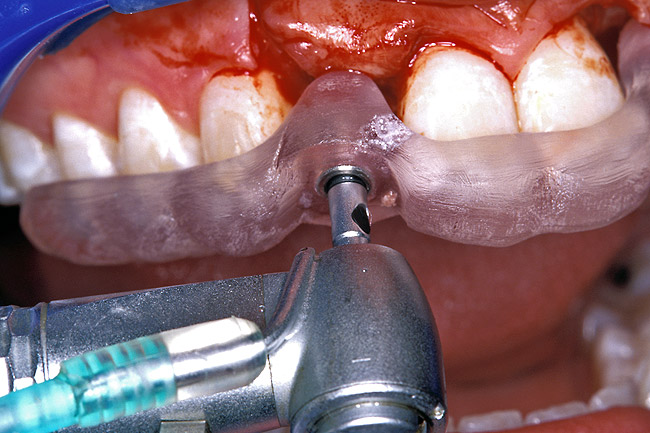

Before the day of surgery, the patient was seen by the orthodontist for the removal of the orthodontic brackets. The patient still was not pleased with the position of the two centrals, and it was determined that this would be addressed after implant placement (Figure 13A). The anatomical variations of the crestal tissue and lack of interdental papilla can be appreciated in the close-up views of the right and left sites (Figure 13B and 13C). There were no surprises on the day of surgery as all of the decisions were made during the planning phase, before the scalpel ever touched the patient. The occlusal view of the CT 3D model revealed the wider alveolar ridge on the right side and thinner crest on the left side (Figure 14A). This was confirmed when the full thickness mucoperiosteal flaps were elevated, and the underyling bone revealed (Figure 14B). The tooth-borne templates were designed to facilitate the drills and drilling sequence specific to the diameters of the predetermined implants (Figure 15A). Each template contained an embedded 5-mm long stainless steel tube, which was approximately 0.2-mm wider than each drill (just wide enough to allow for the drills to rotate freely). Once positioned over the natural teeth, the template was secure and offered precision accuracy in transferring the implant locations from the original software-designed plan, allowing the potential for internal and external irrigation (Figure 15B). The 3.7-mm diameter Tapered Screw-Vent implant drilling sequence requires three drills: pilot, intermediate, and final sizing. Thus, three separate templates were fabricated to a.commodate these sizes. The templates were removed easily and replaced with the next sequential size in less time than it takes to change the drill on the surgical handpiece. After the osteotomies had been.completed, the implants were delivered to the site (Figure 16A and Figure 16B). For this internal hex connection implant, the author r.commends that the flat of the antirotational hex be positioned to the facial for proper orientation of the restorative.components (Figure 17A). Preprepared margins were created from a milled titanium fixture mount transfer post, which was delivered to the implant as support for an immediate transitional restoration. The facial “dot” helped confirm the orientation of the abutment to the facially positioned flat side of the internal hex connection (Figure 17B). Before cementation of the transitional acrylic restorations, a closed-tray, fixture-level impression was made, and a soft-tissue model fabricated.

Figure 15a  A surgical template was derived from the final treatment plan created in the software, which facilitated (A) the drilling sequence and (B) precise location of placement.

Figure 15a

Figure 15b  A surgical template was derived from the final treatment plan created in the software, which facilitated (A) the drilling sequence and (B) precise location of placement.

Figure 15b